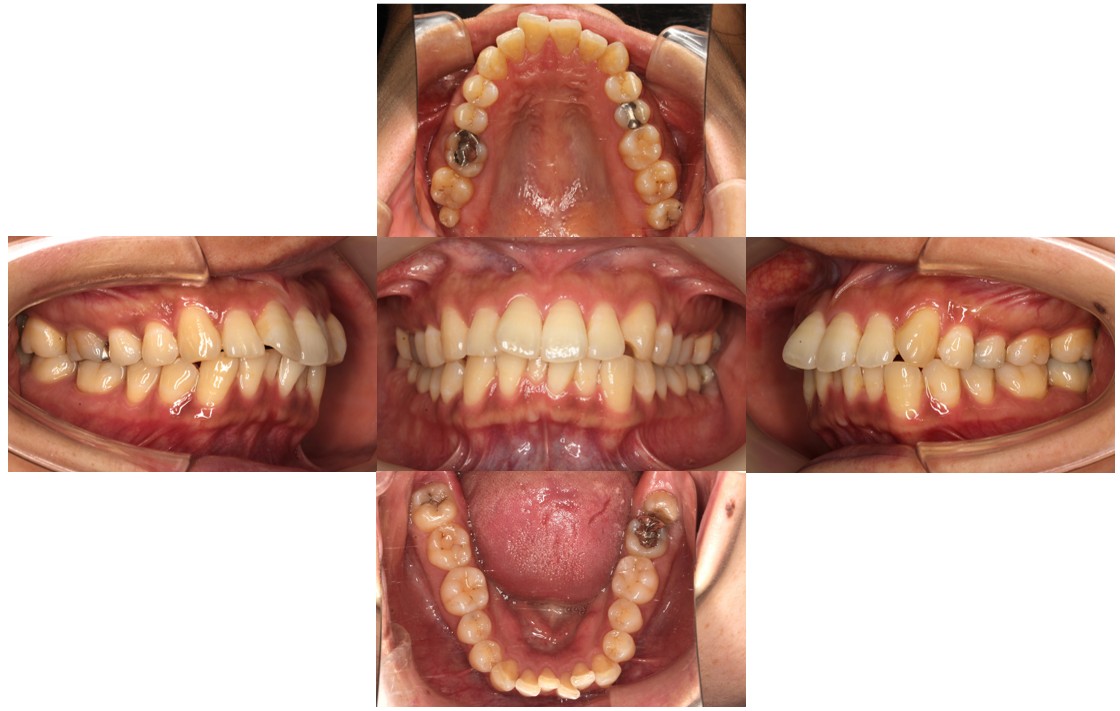

初診時の口腔内の状態です。

上顎の前歯が出ていることにお悩みでご来院されました。